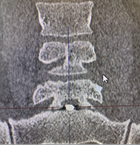

Пациент П., 05.05.2025 г. при взрыве снаряда получил слепое проникающее в позвоночный канал осколочное ранение пояснично-крестцового отдела позвоночника. В течение двух месяцев пациенту оказывалось консервативное лечение. 13.07.2025 г. пациент поступил на лечение в ГВКГ им. ак. Н.Н. Бурденко. При обследовании на КТ выявлен осколок металлической плотности в межтеловом промежутке по срединной линии у заднего края тел на уровне пятого поясничного и первого крестцового позвонков. Осколок прошел через междужковый промежуток сзади по краю фасеточного сустава. У больного имелась клиника болевого синдрома в пояснично-крестцовом отделе позвоночника во время движений и парестезий в проекции S1 корешка. Силовых расстройств не было.

Рис. 1 КТ-картина расположения осколка в трех проекциях.